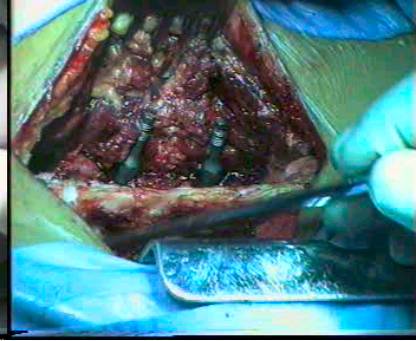

(二)手术治疗

1、指征:(1)症状、体征严重影响生活、工作,经系统保守治疗3个月以上明显无效者。(2)神经根和马尾神经广泛被压受损或瘫痪者。(3)腰椎间盘突出合并腰椎管狭窄者。(4)椎管狭窄合并腰椎峡部不连与滑脱。(5)经椎管造影、CT、MRI证实有局部明显狭窄伴有相应的临床症状者。

2、原则:(1)腰椎管狭窄症的治疗以手术为主,对椎管及神经根管准确而彻底的减压是治疗成功的关键。(2)术前应明确定位,减压的区域应是引起相应的临床表现的部位,对所有狭窄节段和部位进行充分减压。(3)在彻底解除压迫因素前提下,尽可能的少破坏结构,尽量保持脊柱的稳定性。(4)对于多节段椎管狭窄病人,减压术后对脊柱稳定性影响较大时,应同时作腰椎内固定。(5)腰椎管狭窄合并腰椎不稳的病人,在彻底减压同时亦行腰椎内固定术。(6)术中发现硬膜囊增厚、纤维化等病变时,应切开硬膜,行神经探查、松解术。

3、方法:单纯黄韧带切除术;局限性腰椎管及根管后方减压术;常规腰椎管减压术;腰椎管扩大减压术;腰椎管成形术;腰椎管减压、内固定术。

腰椎管减压内固定术